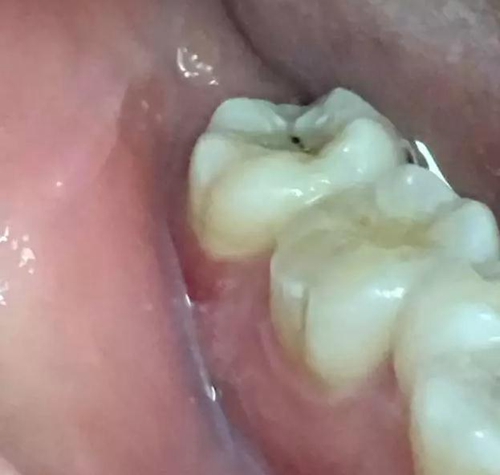

圖1.患者自述右側(cè)下后牙牙齦紅腫,咀嚼不適。術(shù)前口內(nèi)像:37頰側(cè)牙齦紅腫

10.jpg